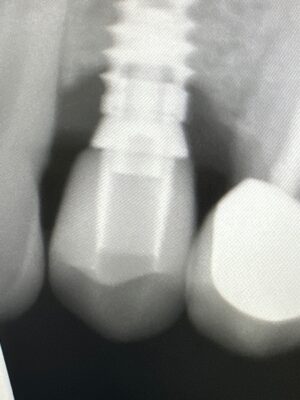

Jeremy started the discussion First complication in the forum Complications 3 years ago

Hey, I’m new here so I thought I would kick off the ‘complications’ with one that I have right now. I placed a Biohorizon implant at #12 around 6 months ago and restored with a tibase and emax crown. I’m new to implants so no implant expert by any means, but this seems like quite a bit of bone loss to already have at this stage. Sorry I dont…